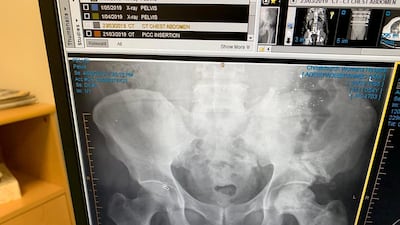

He shows off an X-ray proudly, pointing out an almost polka-dot array of shrapnel still lodged in his side and a cavernous fracture in his pelvis.

Mr Sami flies back to the UAE on Friday to resume his job as a director at Aecom, and he will carry a clearance letter for airport security to prove that the metal setting off the detectors is inside him, rather than on him.